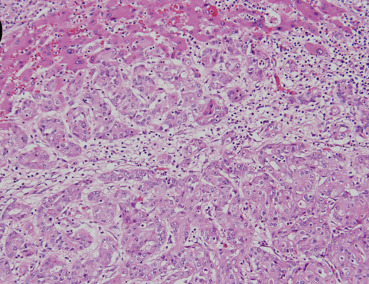

Physical examination demonstrated a thin woman. Her height was 158 cm and weight 48 kg. Her abdomen was soft without rebound tenderness. The laboratory tests were normal, apart from hypokalemia (K 3.4 mmol/L, normal range 3.5–5.3 mmol/L) and normocytic anemia (Hb 11.9 g/dL, normal range 12–14 g/dL). An esophagogram demonstrated a markedly dilated esophagus with a “bird-beak” appearance at the GE junction (Fig. 2 ). Idiopathic achalasia was preliminarily diagnosed based on the above findings, although the patients age and short duration of symptoms were not consistent with the diagnosis. Repeated EGD demonstrated a very tight GE junction (Fig. 3 A) with retention of some food residues and pills in the lower third of the esophagus (Fig. 3 B). Besides, the endoscope could not pass the GE junction into the stomach. However, esophageal manometry demonstrated a normal pattern of esophageal peristalsis. Based on the endoscopic findings and manometric features, pseudoachalasia was suspected. Abdominal computed tomography demonstrated a hypovascular tumor in the left lobe of the liver (Fig. 4 A, arrows). Moreover, the tumor encased the lower end of the esophagus (Fig. 4 B, arrows). Thus, the diagnosis of pseudoachalasia caused by liver tumor was made. At laparotomy, the liver tumor was deemed unresectable and biopsy specimens were taken. A pathological examination of the biopsy specimens showed cuboidal tumor cells with pleomorphic and hyperchromatic nuclei arranged in a ductular or glandular pattern within the desmoplastic stroma, the findings being consistent with cholangiocarcinoma (Fig. 5 ). Finally, the patient died due to disease progression 1 year later.

Pathological examination of the biopsy specimens of the tumor demonstrates ...

Figure 5.

Pathological examination of the biopsy specimens of the tumor demonstrates cuboidal tumor cells with pleomorphic and hyperchromatic nuclei arranged in a ductular or glandular pattern within desmoplastic stroma, confirming the diagnosis of a cholangiocarcinoma (hematoxylin and eosin; original magnification 200×).